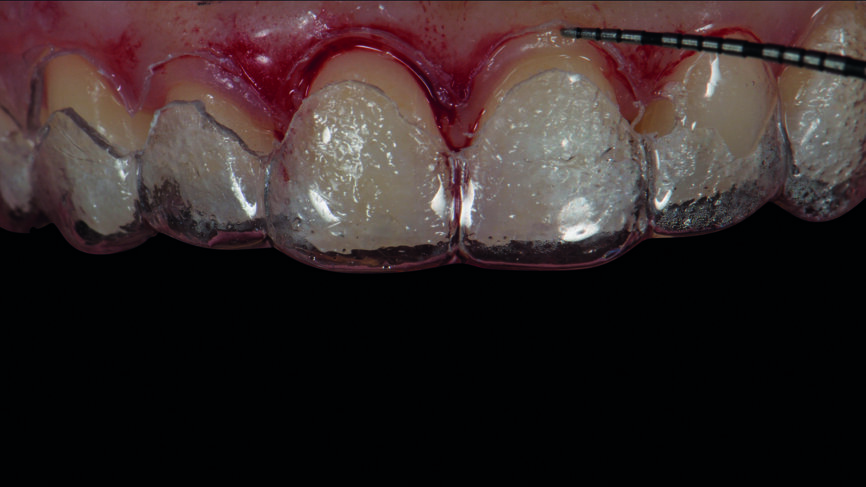

Après une période de stabilisation des tissus d‘une durée de sixmois (Fig.7), un mock-up a été fabriqué au fauteuil avec le composite Telio CS C&B (Ivoclar Vivadent) (Figs. 8a et b), et les dents ont été préparées avec des clés en silicone (Figs. 9a–c). Des empreintes classiques en polysiloxane de vinyle (Fig. 10) ainsi que des empreintes numériques (scanner TRIOS de 3Shape) ont été prises (Fig. 11).

Une prothèse provisoire a été réalisée numériquement en Telio CAD (Ivoclar Vivadent) dans l‘unité d’usinage CNC select de Wieland Dental. La conception a été réalisée à l‘aide du logiciel DentalDesigner, version 2015, de 3Shape (Figs. 12a et b). Deux jeux de restaurations définitives ont été fabriqués.

Le jeu de facettes en céramique feldspathique a été fabriqué en IPS Style (Ivoclar Vivadent) sur un modèle en plâtre-pierre, tandis qu‘un bloc IPS Empress CAD Multi (Ivoclar Vivadent) a été utilisé pour le jeu numérique (Figs. 13 et 14). Les deux jeux ont été évalués en bouche avec une pâte d‘essai afin de comparer les propriétés optiques des facettes feldspathiques et des facettes réalisées en technique CFAO (Figs. 15a–c).